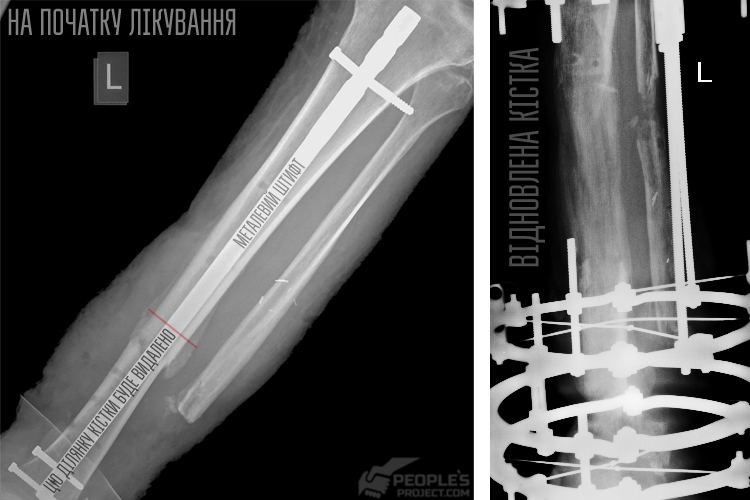

Читайте також: Життя після фронту: унікальна можливість поставити українського бійця на ноги